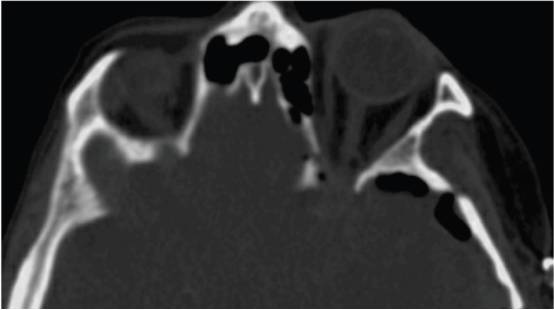

薄层MRI扫描(包括脂肪抑制序列)可用于评估眼眶受累的程度。CT的骨窗和薄层扫描可用于衡量骨浸润或骨增生的程度。与眼整形外科同事讨论有助于评估视觉和眼球突出的基础状态。如果大范围切除受累骨质,可能需要重建眶壁和外侧颅盖骨,术前应准备好个体化定制的植入物。

为识别血管和脑实质水肿,T2加权MR影像也是必须的。外侧蝶骨嵴脑膜瘤,在手术早期即可处理肿瘤血供(主要来自脑膜中动脉),通常无需术前栓塞。

图1. 上图为一个典型的左侧外侧蝶骨嵴脑膜瘤伴骨质增生。下图为右侧蝶眶脑膜瘤伴显著的蝶骨嵴、床突和眶壁增生,导致眼球突出。为长期的控制肿瘤并改善眼球突出,有必要同期切除硬膜内肿瘤和增生的骨质。